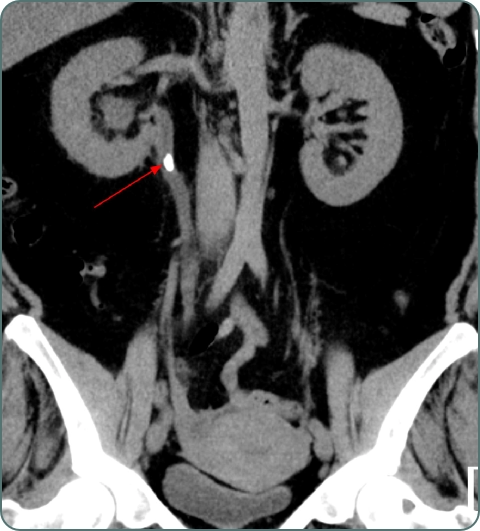

CT Scan

Detailed imaging for kidney stones, tumors, and complex urological conditions. CT urogram provides comprehensive urinary tract evaluation.